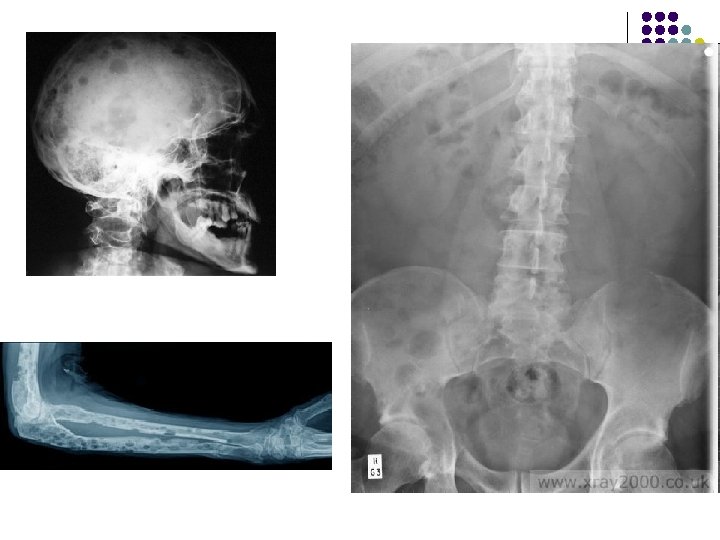

Методы исследования l l l Рентгенография. Компьютерная томография - диагностика поражений костных структур позвоночника и позвоночного стеноза, степень визуализации грыж дисков незначительна и уступает магнитно-резонансной томографии. Информативность метода снижается также тем, что производятся только поперечные срезы, поэтому необходимо знать уровень поражения для уменьшения лучевой нагрузки на пациента. Магнитно-резонансная томография - метод выбора для выявления грыж межпозвонкового диска и протрузии диска и в отличие от КТ не связана с лучевой нагрузкой. МРТ дает возможность проведения как поперечных, так и продольных срезов, что увеличивает информативность. МРТ визуализирует компрессию корешков и степень дегенерации самого диска (протрузию, пролапс и секвестрацию). При МРТ четко разграничиваются экстра- и интрадуральные структуры и хорошо выявляются латеральные грыжи диска.

Рентгенологические критерии